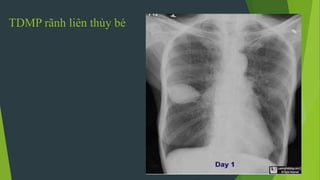

TDMP rãnh liên thùy bé

Tràn dịch màng phổi khu trú

 Có thể khu trú trên vòm

hoành,

 Góc tâm hoành

 Rãnh liên thuỳ

 Trung thất hoặc thành ngực

 Vùng nách